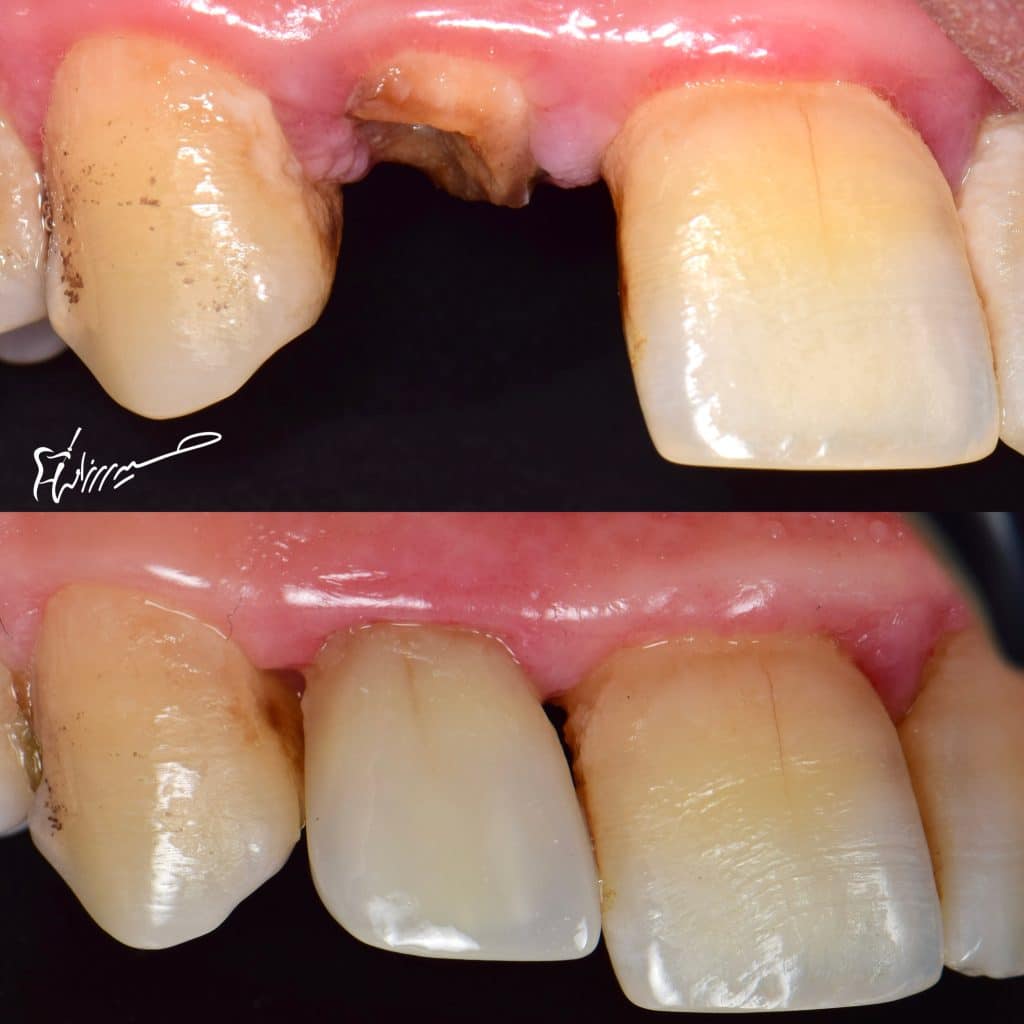

polyethylene fibre (ribbond ) The material has a three

dimensional structure due to the leno weave or triaxial braid

These features provide mechanical interlocking of

the resin and composite resin at different planes, thereby

enabling a wide processing window. In addition, micro

cracking is minimised during polymerization of the resin , also it’s fracture tough material.

Short fiber reinforced composite (ever x ) also it’s fracture tough material.

With this magic materials , we need excellent binding material to bond them to the tooth structure,

SE bond from kurrary is a gold standard and can work in perfect way .

CDD for definite caries removal

DWT for optimum dentin bond